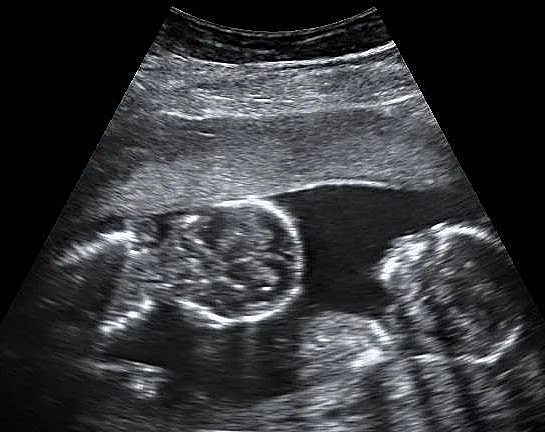

ארה"ב: כשמיה וושינגטון ילדה תאומים ב-2010, משהו לא היה נראה לה בסדר. התאומים כלל לא נראו זהים והיא ובן זוגה רצו לוודא את העניין. לאחר בדיקת אבהות היא הבינה את גודל "ההפתעה" - התאומים, שנולדו בהפרש של 7 דקות הם מ-2 אבות שונים. המצב הנדיר נגרם כאשר 2 ביציות שונות מופרות באותו מחזור ביוץ בגוף האם, אך כל ביצית מזרע אחר. איך זה קרה? את זה אתם כבר יכולים לנחש לבד.

רופאים מעריכים כי מקרה שכזה מתרחש ביחס של 1 למיליון מכל לידת תאומים, אך רוב הפעמים ההורים לא בודקים זאת ולכן אין סטטיסטיקה מדויקת לגבי כמות הפעמים שזה קורה. ההחלטה לערוך בדיקת אבהות הייתה משותפת למיה ולבן זוגה - שהוא אביו הביולוגי של רק אחד מהתאומים, אך הוא מצידו נשאר עם מיה והחליט לגדל את 2 הילדים כאילו היו שניהם דם מדמו.